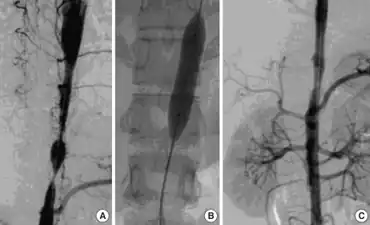

| Left anterior oblique angiographic image of Takayasu's arteritis showing areas of stenosis in multiple great vessels | |

Although the cause of Takayasu arteritis is unknown, the condition is characterized by segmental and patchy granulomatous inflammation of the aorta and its major derivative branches. This inflammation leads to arterial stenosis, thrombosis, and aneurysms.[3] There is irregular fibrosis of the blood vessels due to chronic vasculitis, leading to sometimes massive intimal fibrosis (fibrosis of the inner section of the blood vessels).[5] Prominent narrowing due to inflammation, granuloma, and fibrosis is often seen in arterial studies such as magnetic resonance angiography (MRA), computed tomography angiography (CTA), or arterial angiography (DSA).

Diagnosis is based on the demonstration of vascular lesions in large and middle-sized vessels on angiography, CT scan, magnetic resonance angiography or FDG PET.[11] Seeing abnormal diffuse arterial wall thickening, the 'macaroni sign', with ultrasound is highly suggestive of the condition.[12] FDG PET can help in diagnosis of active inflammation not just in patients with active Takayasu arteritis prior to treatment but also in addition in relapsing patients receiving immunosuppressive agents.[4][13]

Contrast angiography has been the gold standard. The earliest detectable lesion is a local narrowing or irregularity of the lumen. This may develop into stenosis and occlusion. The characteristic finding is the presence of "skip lesions," where stenosis or aneurysms alternate with normal vessels. Angiography provides information on vessel anatomy and patency but does not provide information on the degree of inflammation in the wall.[11]